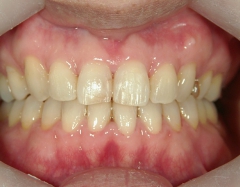

矯正歯科(全顎ワイヤー矯正)治療後

36歳女性 磐田市

在住

治療期間2年6

ヶ月